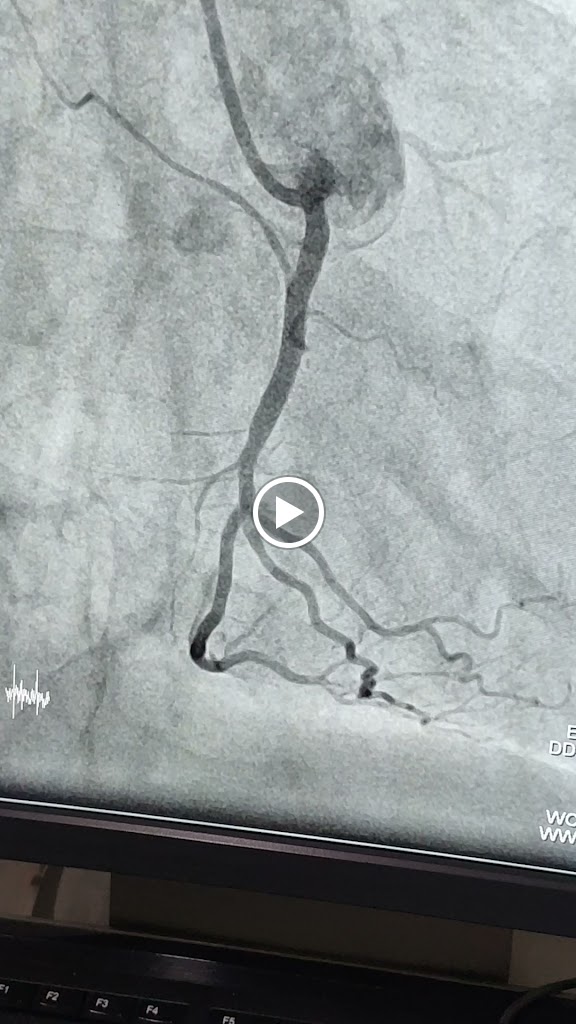

In north bengal debojyoti sarkar is only hope for cardiac patients .....he saved my father's life in 2021 ....in the age of 73 my father have heart attack, he faces massive chest pain & illness ..our family admited him to our local nursing home they told us if possible take him to the better facilated hospital asap....on that pandamic time our family was totally in fear & we lost our hopes & sudden their was a hope ,we contact with him & we reach anandoloke hospital as soon as possible , he just checked my father through angiogram & he told us i will make it....that confident boost us to go through that journey of planting a stent .......after that operation my father is totally out of denger. ..after 4-5 days we brought him back home & few months later we constently in touch with debojyoti sir...till that time to now my father is totally fine & enjoying his retirement life happily......2021-2025 my father till in his observation & guidence ......thank you for saving my father's life........you are the only hope for north bengal people's.......lot's of love & respect for you sir from cooch behar

He is the best in NorthBengal when it comes to interventional Cardiology. His skill on Angioplasty and Angiogram are second to none in North Bengal. Yes he is very busy doctor, a lot of people have complained about his unprofessional behaviour regarding timings. But u also need to understand when a doctor is in OT doing a procedure he cannot just leave a patient with a probe inside just because his OPD timings are on. The patient on the operating table is his top priority then. He goes to Anondoloke as well as Neotia and does angio, we visited him in Medi malland he was right on time. His approach is very calm and he gives u hope. We were very satisfied with him as a doctor. Would recommend everyone but would also advice a lot of patience.